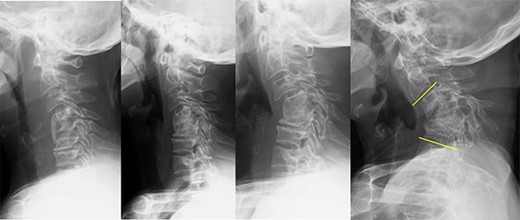

On clinical examination, we observed severe kyphosis (C2–7 angle: −65) with C4–6 fusion. Magnetic resonance imaging (MRI) and computed tomography (CT) myelography revealed C3/4 spinal canal stenosis with C3 anterior slip. Imaging showed two right transverse foramina at the C4 level and a tortuous right VA invaginating into the C4 vertebral body (Fig. 2).

CT myelography, MRI and CT angiography on admission; (A) stenosis at the C3/4 level with C3 anterior slip was observed on magnetic resonance T2-weighted images, and (B) the C4–6 vertebrae were fused into a single mass; note local kyphosis and scoliosis due to vertebral collapse, and a transverse slice at the C4 level showed two transverse foramina on the right side, and (C) the right VA invaginating into the C4 vertebral body was shown in a transverse slice at the C4 level on CT angiography.